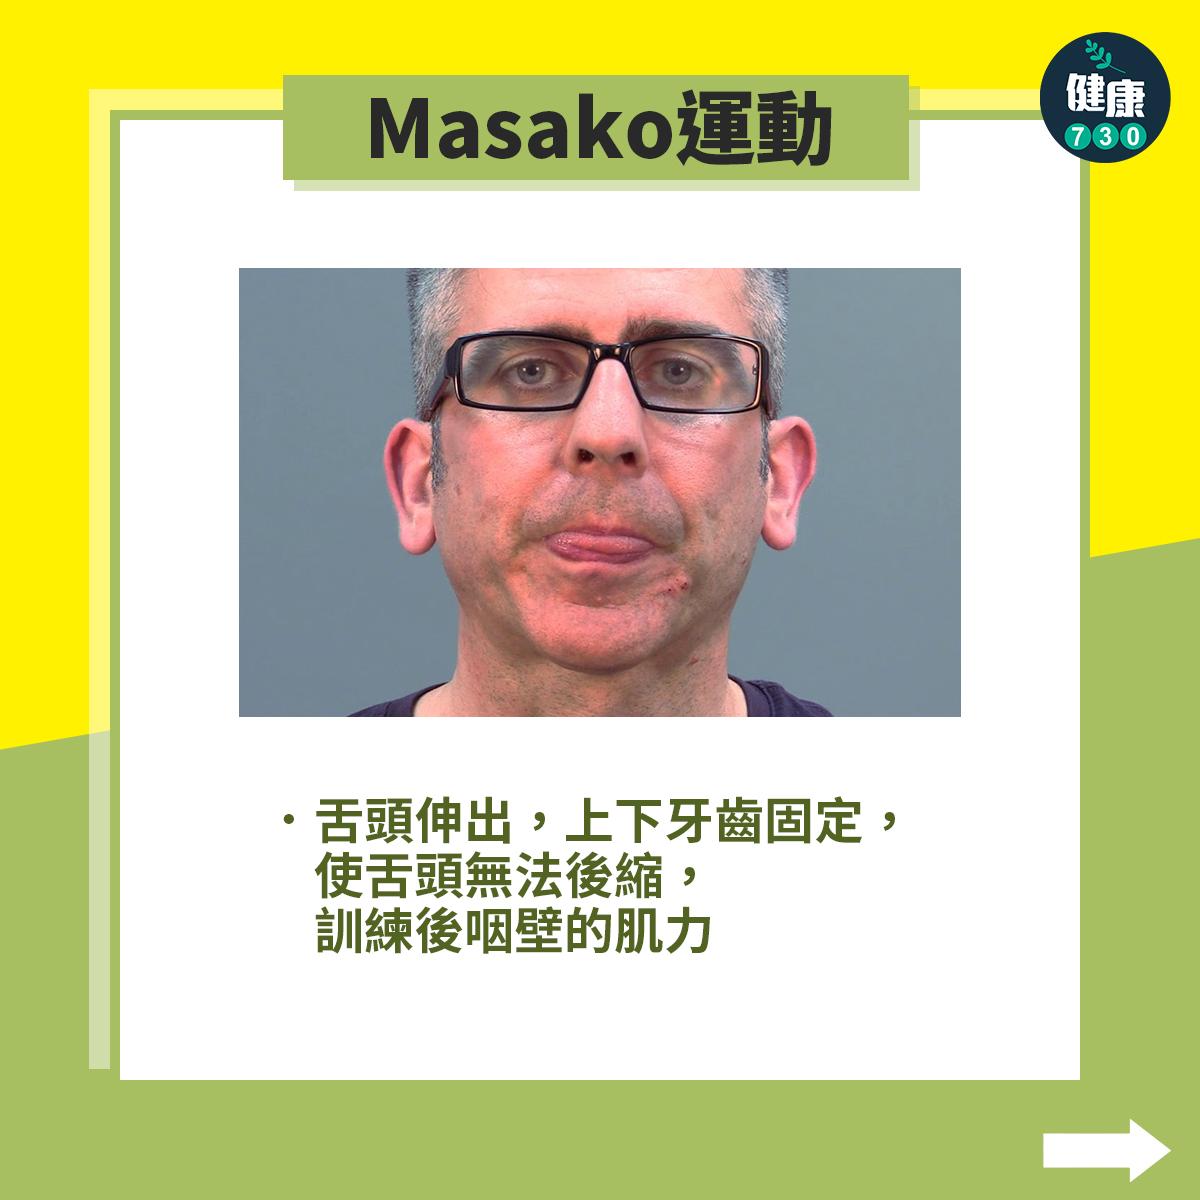

中風復健|5招改善中風後吞嚥困難